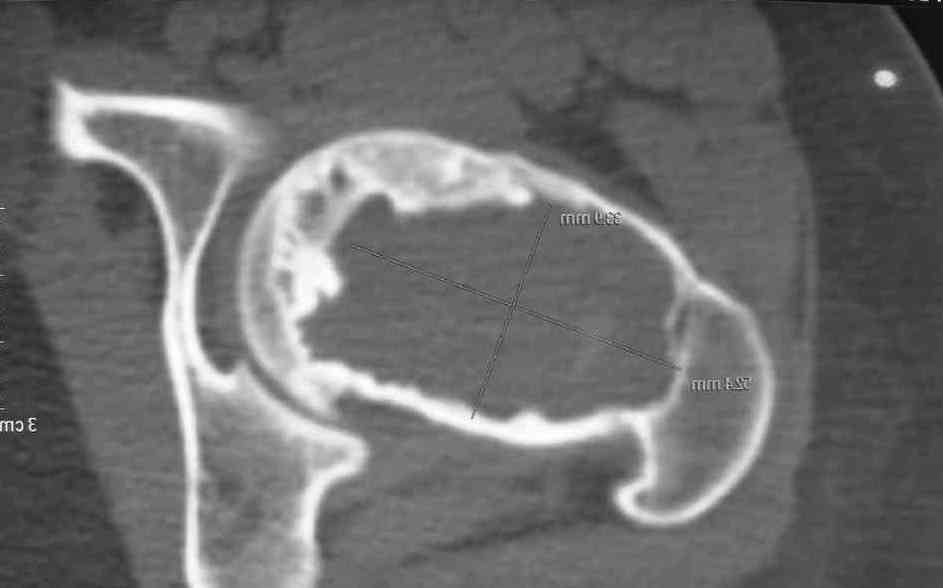

Больная Л., 23 года. Из анамнеза:со слов больной в 2006 г. появились боли правой н/конечности, обратилась поместу жительства к хирургу, было выполнена МРТ поясничного отдела позвоночника,назначено физиолечение. Через 2 месяца боли прекратились, через 4 месяца рецидив болевого синдрома. С 2006 – 2010 проводилось консервативное лечение по поводу остеохондроза поясничного отдела позвоночника. В октябре 2010 г. боли усилились. Выполнены Ro и КТ правого тазобедренного сустава, выявлен очаг патологической перестройки. Была направлена на консультацию в УНИИТО. В УНИИТО виюне 2011 г. поставлен дифференциальный диагноз между фибромой, солитарной костнойкистой и гигантоклеточной опухолью.

Клиника и течение заболевания похожи на однокамерную кисту. Больная молодая, желательно сохранить собственную головку. Надо спешить с операцией, иначе скоро произойдет перелом через тонкую стенку. Во время операции внутри будет пустота и небольшое количество жидкой крови.